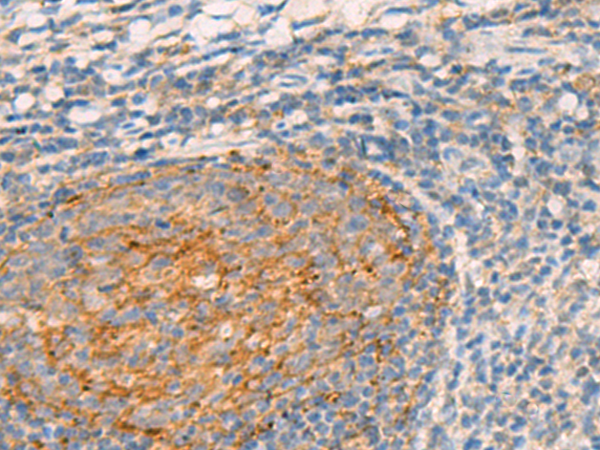

分类: 科研抗体货号: P13536别名: GRP; HSPC159应用: IHC反应种属: Human, Mouse